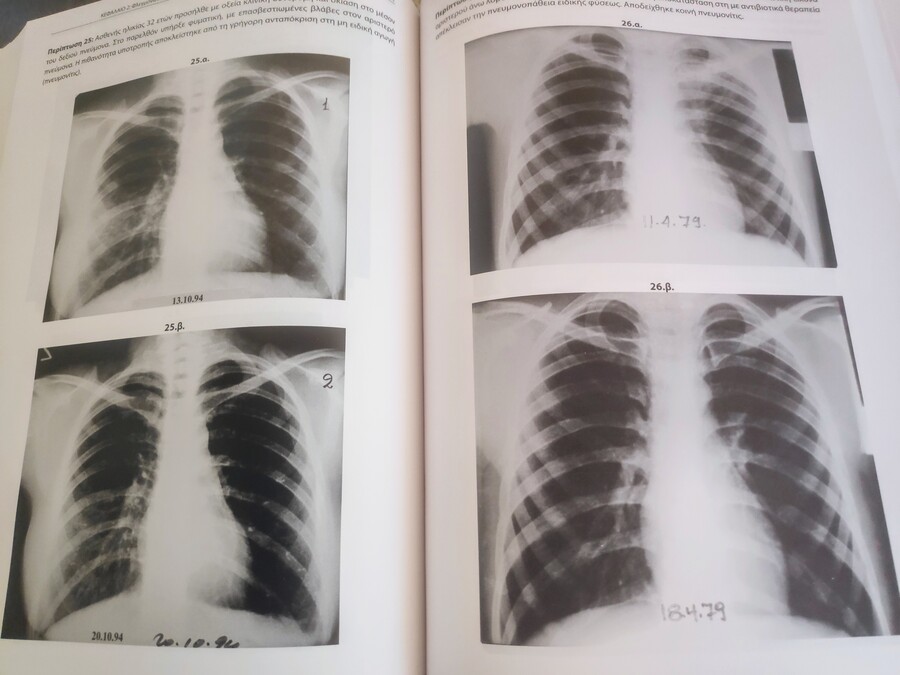

Το βιβλίο “Φυματίωση: Εμπειρίες και συμπεράσματα από την μελέτη της φυματίωσης – Μια περιήγηση στην ακτινογραφία θώρακα” εκδόσεις Ιπποκράτης κυκλοφόρησε το 2020 και γίνεται επίκαιρο όσο ποτέ αποτυπώνοντας πάνω από 2000 περιστατικά, 32.055 φυματιω-αντιδράσεις, 17.009 εμβολιασμούς Β.C.G. αντιμετωπίζοντας νοσηρότητα, διαμόλυνση, ενδονοσοκομειακή οικιακή νοσηλεία, τη φυματική πρώτο μόλυνση, τη διερεύνηση τη φυματική διαμόλυνση, αποτυχίες, υποτροπές, θανάτους, μεταφυματιδιώδεις αλλοιώσεις, καρκινώματα σε ουλή κ.α. ενώ γίνονται αναλυτικές αναφορές στην χειμειοπροφύλαξη για την πρόληψη της νόσου, τα συμπεράσματα αντιμετώπισης της με στόχο την εκρίζωση.